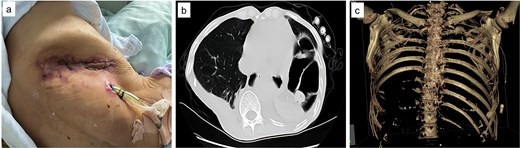

Upon admission, chest computed tomography (CT) and gastroscopy confirmed persistent esophagopleural fistula and empyema (Fig. 1a-c). A multidisciplinary team formulated a stepwise management plan: Stage 1: Under CT guidance, a chest drainage tube was reinserted. The nutrition team optimized nutritional status, correcting hypoalbuminemia and anemia. Thoracic drainage fluid culture revealed multidrug-resistant Pseudomonas aeruginosa; based on antimicrobial committee advice, local treatment (twice-daily 250-ml saline irrigation) was prioritized over systemic antibiotics. Stage 2: After 1 month, the drainage fluid became clearly transparent. However, CT showed unchanged fistula and cavity (Fig. 2a). Thus, a surgical plan was developed. CT-based three-dimensional reconstruction (Fig. 2b-d) guided surgery. Under general anesthesia, a 15-cm incision was made over the 10th rib. The latissimus dorsi muscle flap was dissected with preserved blood supply (Fig. 3a). Intercostal structures were preserved. The 9th and 10th ribs were transected 2 cm from the purulent cavity margin; the 11th and 12th ribs, 2 cm from the vertebral column. After thorough irrigation, a washable drainage tube was placed with its distal end toward the fistula. Muscle flaps were inserted into the cavity and sutured with antibacterial Vicryl (Fig. 3b and c). Finally, the incision was sutured (Fig. 3d). Stage 3: Skin depressions were compressed with cotton pads and a chest strap for 2 weeks (Fig. 4a). Sensitive antibiotics were administered for 2 weeks; intermittent saline irrigation-maintained drainage patency. The drain was removed at 3 weeks. Postoperative CT showed satisfactory recovery (Fig. 4b and c); the duodenal tube was removed 1 month later, and the patient resumed a normal diet gradually. As of July 2025, he remained symptom-free with no recurrence.

Postoperative images. (a) Fourteen days following the surgical procedure, the wound exhibited satisfactory healing. (b) One month after surgery, during the preparation for removal of the nasointestinal tube, a follow-up chest CT scan revealed that the abscess cavity had been completely filled. (c) Visual documentation of the removal of ribs 9th to 12th.